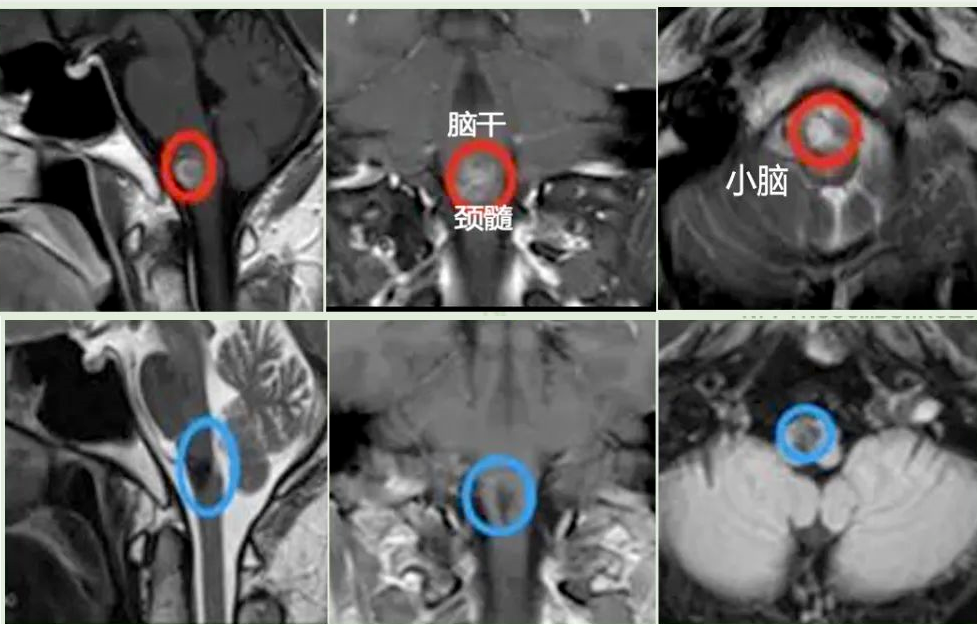

术前术后影像对比,第一排为术前,第二排为术后。

于是在2019年6月,在国内神经外科医生的协同配合下,INC德国巴特朗菲教授主刀为宋先生进行了手术。手术过程十分顺利,脑干延髓海绵状血管瘤最终全切。

术后第2天:从ICU转出至普通病房,无新发神经功能损伤。

术后第90天:头痛、行走不稳、复视等症状基本消失。

术后2年:神经功能恢复良好,生活如常,甚至每天都会坚持慢跑5-6公里。